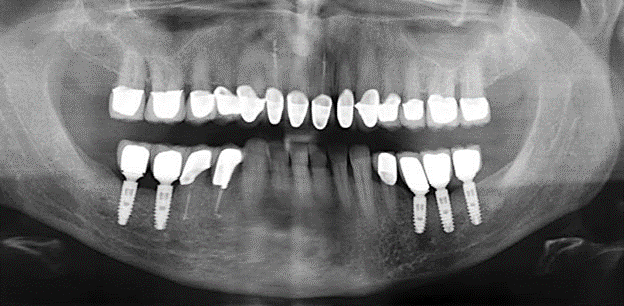

Standardised and regular risk-adapted care in the scope of SPT is the key to treatment success for the clinical long-term success in periodontically compromised patients. This is particularly true for patients fitted with implants following successfully completed periodontal treatment (Fig. 11a and b).